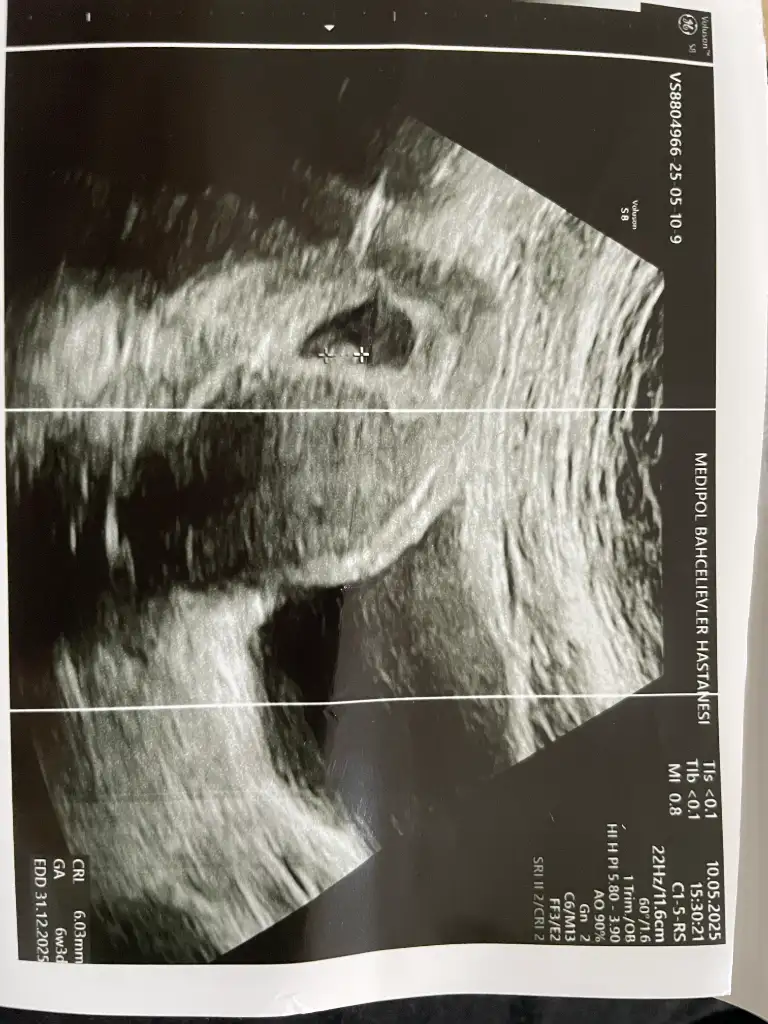

Buda 8 haftalık heErkek olduğunu düşünüyorum

KızBuda 8 haftalık he